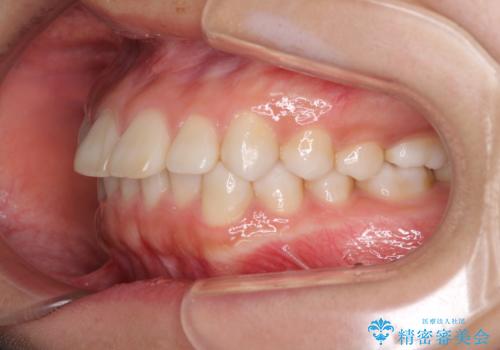

インビザラインによる軽度な出っ歯の矯正治療

- 上の前歯の出っ歯を治したいとのことで来院された患者様です。

上下顎ともにIPR(歯と歯の間を削る)と歯列全体の拡大によって口元が引っ込むように設計し、インビザラインにより治療を行うこととしました。

どこまで口元を引っ込めることができるのか、患者様自身も正直分からない部分があったため、少しずつ治療ゴールを変更しながら仕上げていきました。

気になっていた前歯の飛び出した印象は、最終的にはスッキリと引っ込み、大変満足していただきました。